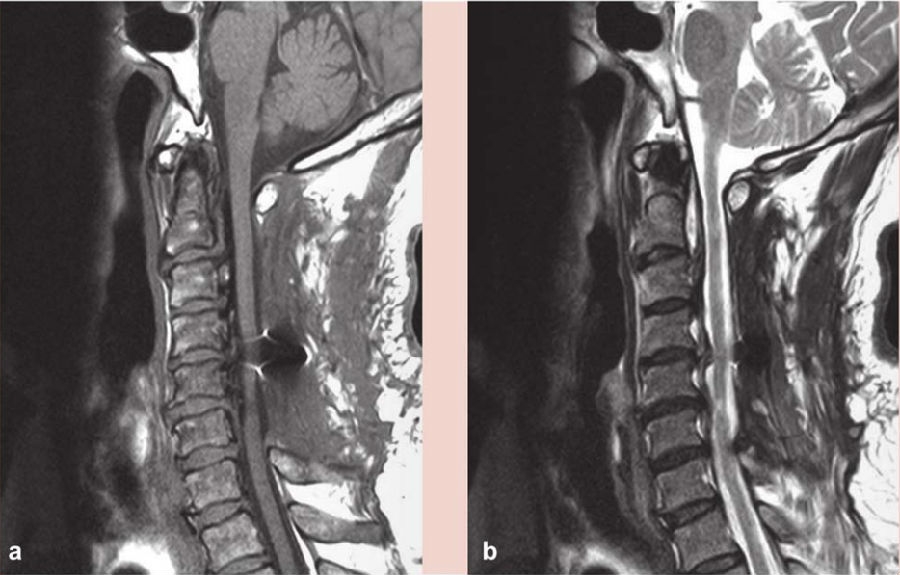

术后给予激素、补液及支持对症治疗,右手麻木较前好转,右侧肢体出现无力,左侧肢体出现麻木,疼痛感不明显,经康复治疗后,右手环指及小指仍感无力,余肢体麻木及无力较前好转,仍对生活及工作有影响。复查颈椎磁共振(MRI)示:C2-6椎板减压及内固定术后状态(图2),C4-6脊髓稍变细,以 C5-6节段显著,C2-6后纵韧带钙化(图2);CT三维重建钉棒系统位置良好(图3);术后3个月复查磁共振(MRI),髓内异常信号较前缩小,颈椎生理曲度变直(图4);术后11个月复查磁共振(MRI)示C4-5、C4-6椎间盘突出,脊髓受压明显,颈椎生理曲度进一步变直(图5)。

图5 术后11个月磁共振(MRI)示C4-5、C4-6椎间盘突出,脊髓受压明显

a. 矢状位T1像;b.矢状位T2像